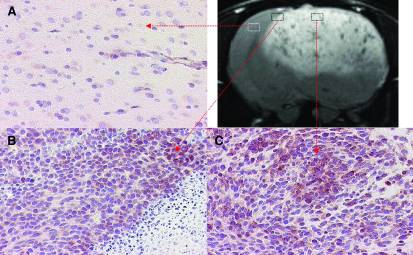

Many focuses of tissue engineering revolve around the basis on cell angiogenesis. Tissue engineered skin grafts are just one example where the success of the tissue is directly correlated to angiogenesis. Towner et al developed a novel idea of assessing cell angiogenesis by monitoring vascular endothelial growth factors (VEGF) with magentic resonance imaging. Magnetite nanoparticles were covalently bound to VEGF probes as a tracer for MR imaging. These probes are a microdevice that have similar characteristics to antibodies, attaching to VEGF but not affecting it. A culture of tumorous cells were placed into the brain of a rat for testing. The hypothesis was that a tumor would have higher levels of VEGF, attracting a large amount of tagged VEGF probes. Tumor growth in the brain tumor was able to be detected by MR imaging in combination with the nanoparticle tagged VEGF probes. Figure 5 shows the MR images of the tumor treated with the tagged VEGF probes. The experiment proved that angiogenesis can be tracked using magnetic resonance imaging in combination with VEGF probes. The rat tested experiment devevloped a new way of monitoring tumor growth as well as other engineered tissues reliant on cell angiogenesis [14].